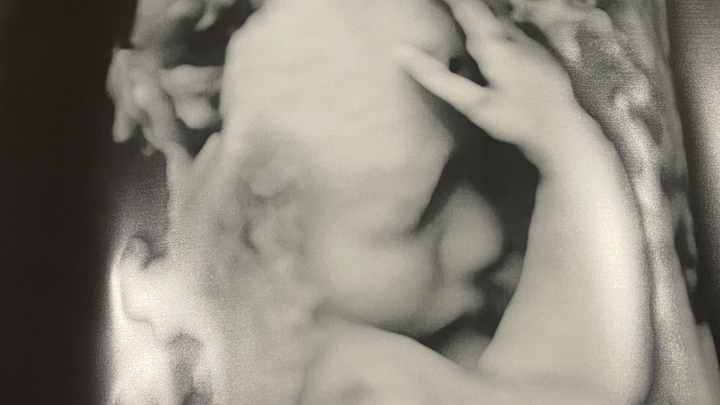

I hate that I even have to make a post like this but a couple weeks ago Jawaun and I found out our babygirl has a rare congenital heart defect called Taussig Bing but it’s a little worse than what you’ll find on google about the condition itself.. because of this rare occurrence her aorta is way smaller than they thought it would be she wont be able to pump any blood through her body so when she is born she will have to have immediate heart surgery and if they can’t do that then it’s straight to the heart transplant list she will be hooked to machines for a while unless they are able to do a successful surgery we will have to deliver her in Chicago at Luries and they will do everything possible to give our babygirl the best chances to live and im trying to cope the best I can but on top of all this news we are now worried about our financial stability being that we will have to travel to Chicago a few times before she is born and stay there a while after she’s born we wanted to start a go fund me just to maybe help out a little to keep our home maintained while we’re gone because we will both have to miss work and neither of our jobs have paid leave i don’t like to ask for help but I believe we will need as much help as we can get when the time comes there are programs we can get into after she is born to help us out but in the meantime I just wanted to try the plan is to induce me when the time comes so I can already be in Chicago and they can take her straight into surgery but on the off chance I have her early they will have to life flight her to Chicago it’s just a lot that I’m not prepared for and I don’t really know how to get prepared for it all funds will go toward gas and home expenses until assistance is available to us